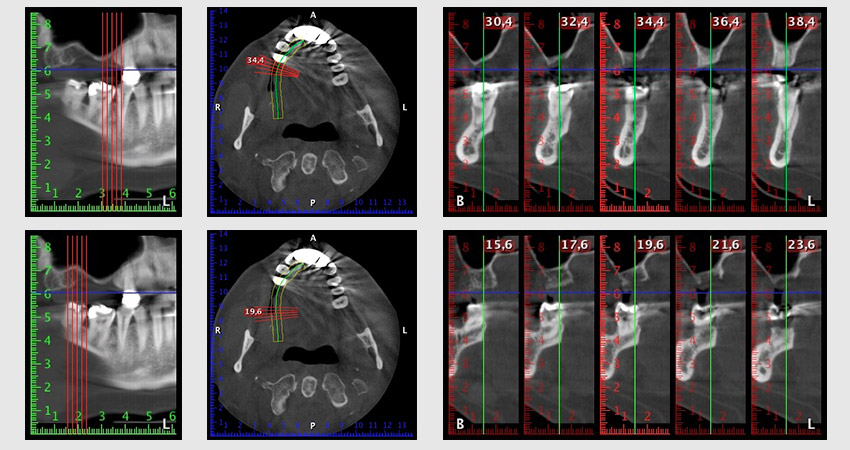

Etwa sechs Monate nach Extraktion der Zähne 16 und 14 wurde zur Planung und Risikominimierung eine digitale Volumentomografie (DVT, Planmeca) erstellt. Hierbei wurde deutlich, dass der Knochen sich nicht in der gewünschten Quantität regeneriert hat (Abb. 2 bis 7).

Um die Augmentation auf Regio 14 einzuschränken, wurde in Absprache mit der Patientin eine Schrägstellung des Implantats 16 nach dorso-kranial geplant (Abb. 8).